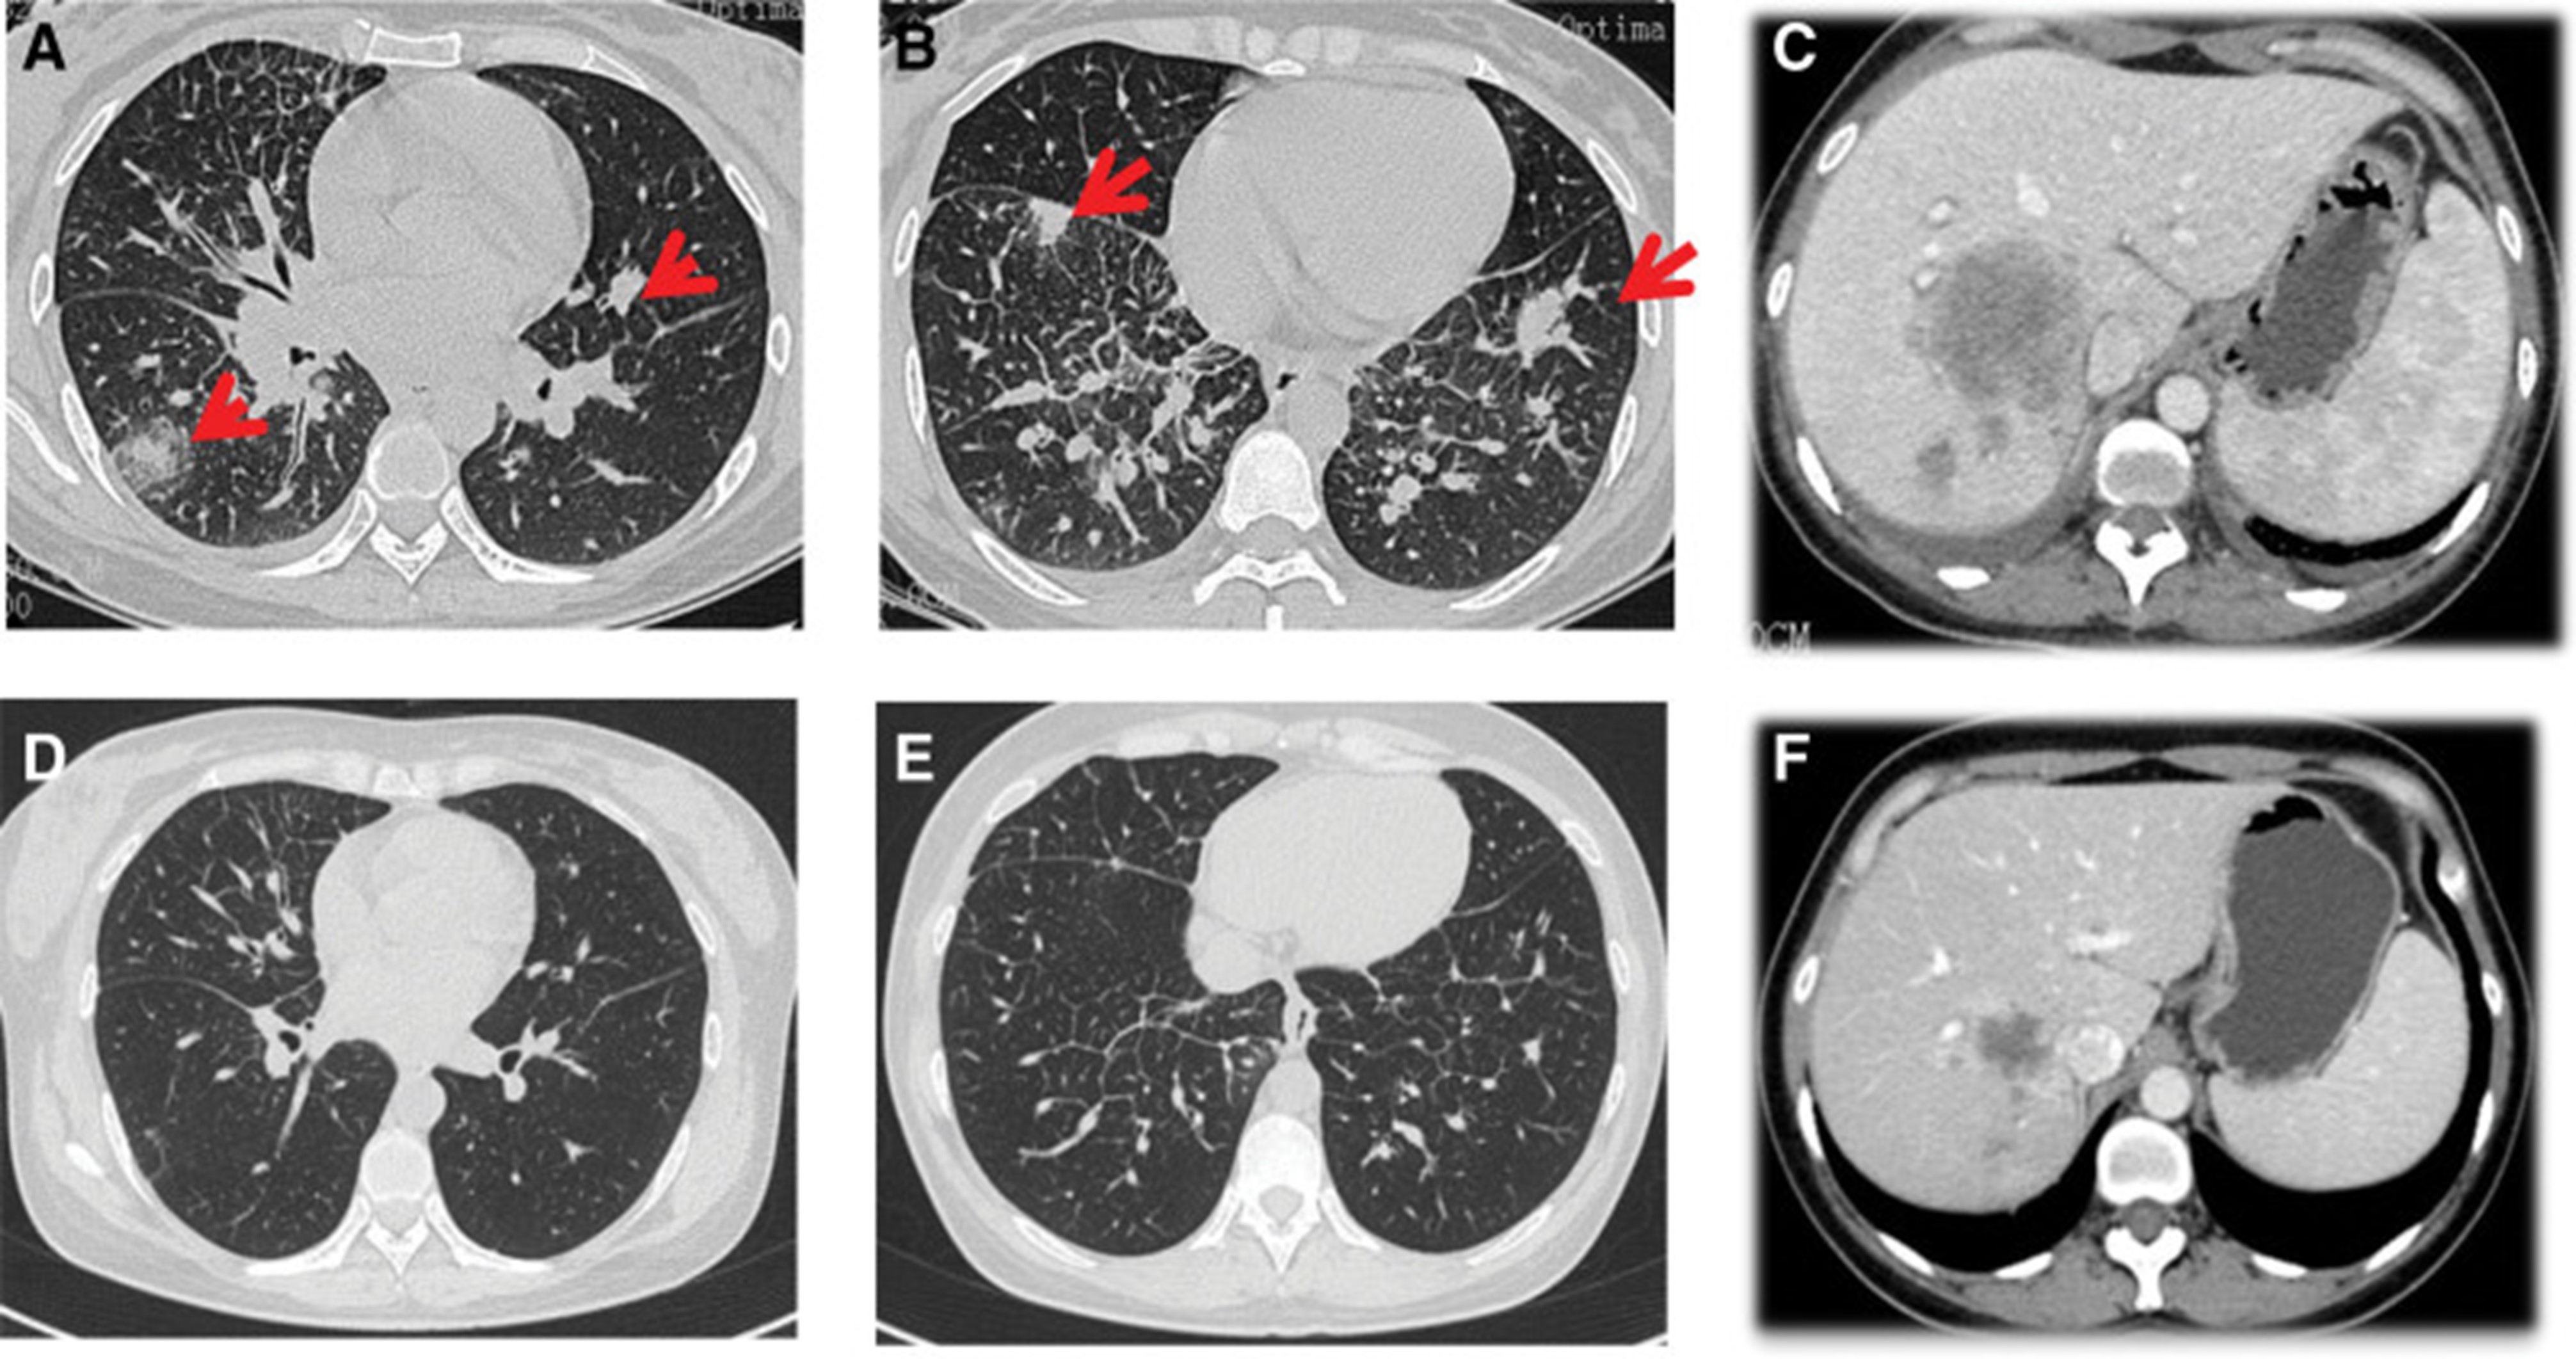

1个月后复查显示肺部和肝内病变进展(图1)。(图 6A-C)(根据RECIST1.1),她的抗肿瘤治疗改为“培姆曲塞加卡铂和贝伐单抗”的治疗一个周期。2020年12月至2021年1月,再次改变患者的治疗方案,这次改为“劳拉替尼联合达拉非尼”靶向治疗。使用 PD 联合胸部和腹部 CT 评估疗效(图 1)。(图 6D-F)(根据 RECIST1.1)。患者无法耐受化疗、靶向治疗、IO 治疗或任何其他积极的抗肿瘤治疗。这是因为患者的一般情况较差,包括发烧、腹痛和胆红素水平升高等症状。随后,给予患者静脉营养、镇痛等对症支持治疗。患者于 2021 年 2 月 4 日去世,总生存期(OS)为 10 个月。

图 6:2020 年 11 月 (A-C) 和 2022 年 1 月 (D-F) 的 CT 扫描。CT = 计算机断层扫描。